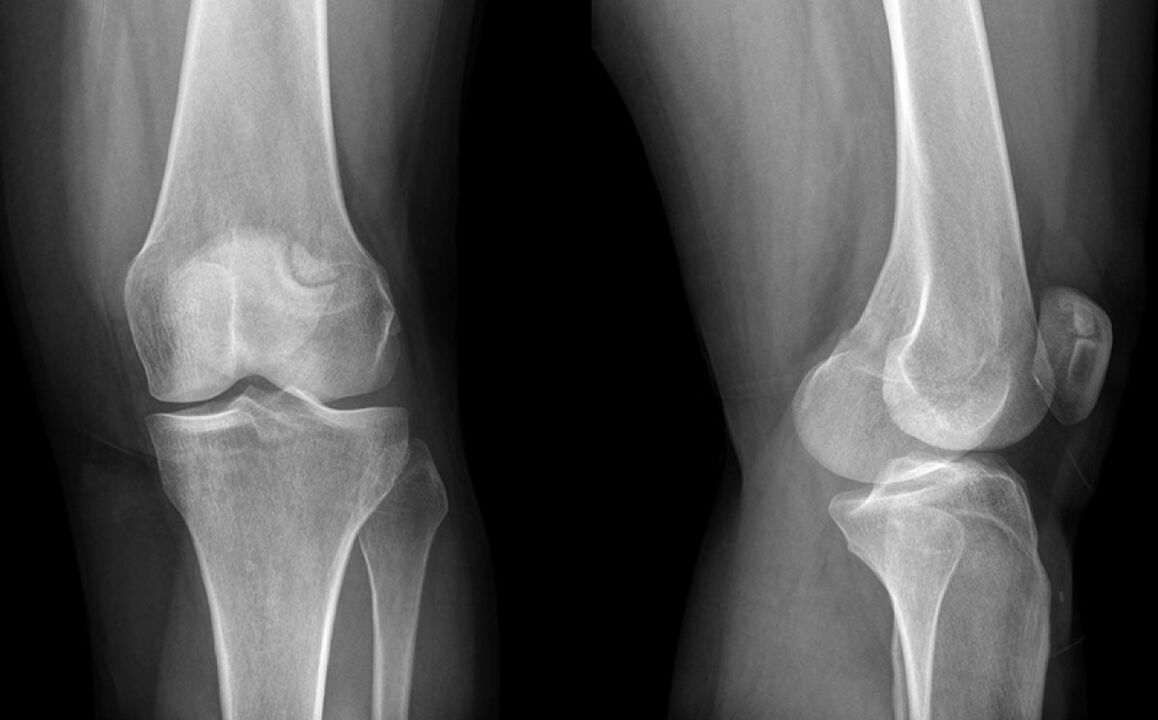

Põlve tegi kolm nädalat haiget. Lõppkokkuvõttes läksin arsti juurde, kes kahtlustas meniski kahju ja saatis X -RAY -le. Diagnoos on põlveliigese artroosi algstaadium.